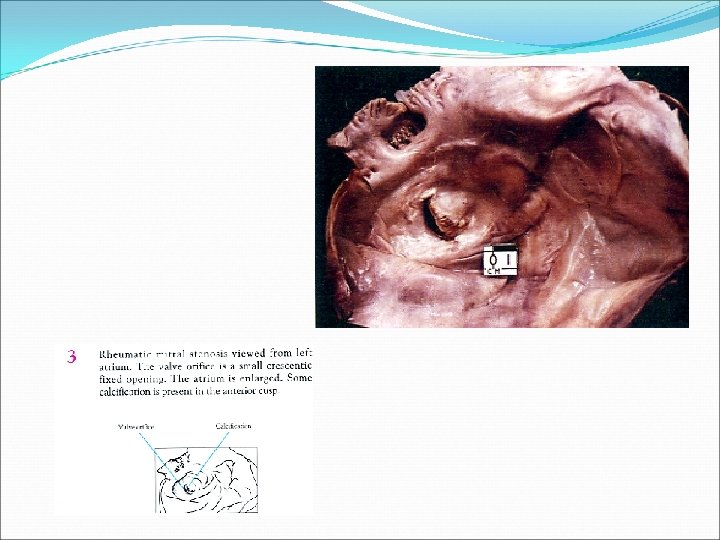

Estenosis Mitral �Es una reducción en el orificio efectivo de la válvula el cual normalmente es de 5 -6 cm 2. �Prácticamente todos los casos son de etiología reumática �Otras causas menos frecuentes son anormalidades congénitas, LES y la mucopolisacaridosis

Consecuencias hemodinámicas de la estenosis mitral �Dilatación auricular severa �Congestión retrógrada del pulmón �Bajo gasto �Ventrículo izquierdo normal